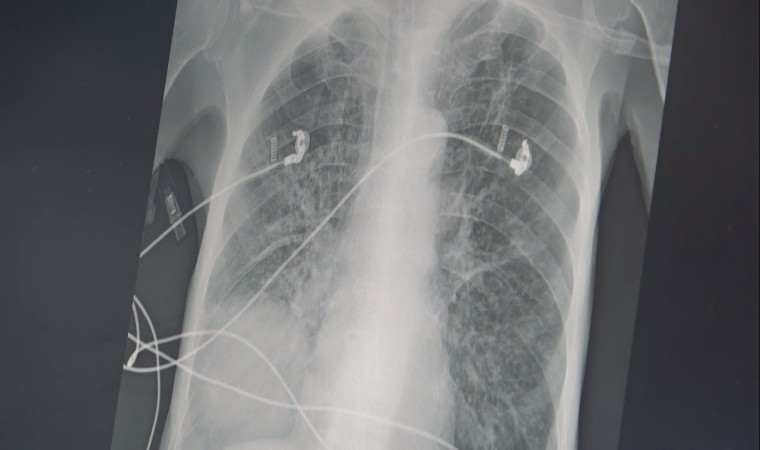

Sigara kullanımın zararlarının insanlara anlatmanın artık etkili olmadığını ifade eden Göğüs Hastalıkları Uzm. Prof. Dr. Şevket Özkaya, balon örneği üzerinde sigaranın verdiği zararı anlattı. Sigara kullanımın ortaokul yaşına kadar düştüğünü söyleyen Prof. Dr. Özkaya, "Ülkemizde 20 yaş üstündeki kişilerin en az yarısı sigara bağımlısıdır ve sigaraya başlama yaşı artık ortaokul çağlarına kadar indi. Sigaranın zararları anlatmak artık insanlarımızı etkilemiyor ama içtiğiniz sigara 2 ölümcül hastalığın yüzde 90 sebebidir. Bunlarda biri KOAH, diğeri ise akciğer kanseridir. Eğer yaşınız 40 üzeri ve içtiğiniz sigara paketi ile kullandığınız yılı çarpar, 20 paket/ yıldan daha fazla ise bu iki hastalık ile her an yüzleşebilirsiniz. KOAH teşhisi alan kişilerin büyük çoğunluğu halen sigara içen veya çok uzun süre sigara içmiş ve bırakmış kişilerdir. Hastalık sinsi ilerlediği için ve sigara bağımlıları öksürük, balgam çıkarma gibi şikayetleri önemsemedikleri için KOAH teşhisi konduğu zaman hastalar akciğer kapasitelerinin önemli bir kısmını kaybetmiş olmaktadırlar" diye konuştu.

Akciğer keseciklerinin tıpkı bir balon gibi olduğuna dikkat çeken Özkaya, "Temiz havayı nefes olarak bu keseciklere aldığınızda şişer ve hava ile dolunca elastik yapısından dolayı içerdeki kirli havayı da tıpkı balonun sönmesi gibi dışarı atar. Bu mekanizma hayat kurtarıcıdır. Ancak sigara içerseniz, kesecik duvarlarınızdaki elastik doku harap olur ve esneme yeteneğini kaybederek tıpkı bu naylon poşet gibi olur ve nefes alırsınız ama balonun elastik yapısı olmadığı için kirli havayı dışarı atamazsınız ve içerde kirli hava kalır. Siz yeni bir temiz havayı nefes le almak istediğinizde keseciklerde temiz havanın gireceği yer kalmayacak ve nefes alamama yani nefes darlığı başlayacak" şeklinde konuştu.

Kişilerin uzun yaşama imkanı da olsa her hücrenin kanserden öleceğini belirten Özkaya, "Sigaranın diğer ölümcül sebebi ise akciğer kanseridir. Biz şunu biliyoruz ki, yaşayan her sağlıklı hücrenin sonu kanser. Eğer diğer hastalıklar, kazalar ve erken ölümler olmasa ve uzun yaşama imkanı olsa her hücre kanserden ölecek. Eğer sigara kullanıyor veya kanserojen maddelere maruz kalıyorsanız, bu kansere yakalanma yaşınızı düşüren bir faktör. Örneğin; 150 veya 170 yaşında akciğer kanseri olacak bir kişi, sigara içtiği için bu yaş 100’e düşüyor. Eğer ailede kanser öyküsü varsa bu yaş daha da düşüyor. Ve 45 yaşından sonra her an kanser gelişmesi ile karşı karşıya kalınıyor. Sigara içmeye hiç başlamayarak bu iki ölümcül nefesten kurtulabilir ya da bırakarak bu iki ölümcül hastalık riskinizi azaltabilirsiniz" şeklinde konuştu.